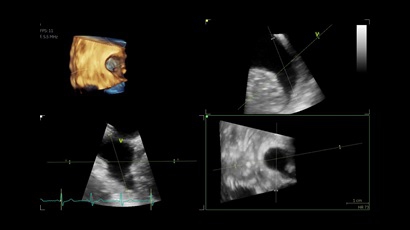

• Vivid IQ 4D с поддержкой технологии объемной реконструкции

• Передовые технологии, такие как 4D чреспищеводная эхокардиография, ЭКГ, стресс-эхо, внутрисердечная ультразвуковая эхокардиография, тканевый доплер и другие.

4D:

Да

• 6VT (биплан/триплан).

• 4D AUTO AVQ - модуль автоматического выравнивания, сегментации и обсчета размеров кольца аортального клапана по объемным данным.

• 4D AUTO LVQ - модуль расчета массы миокарда ЛЖ на основе данных 4D-исследования.